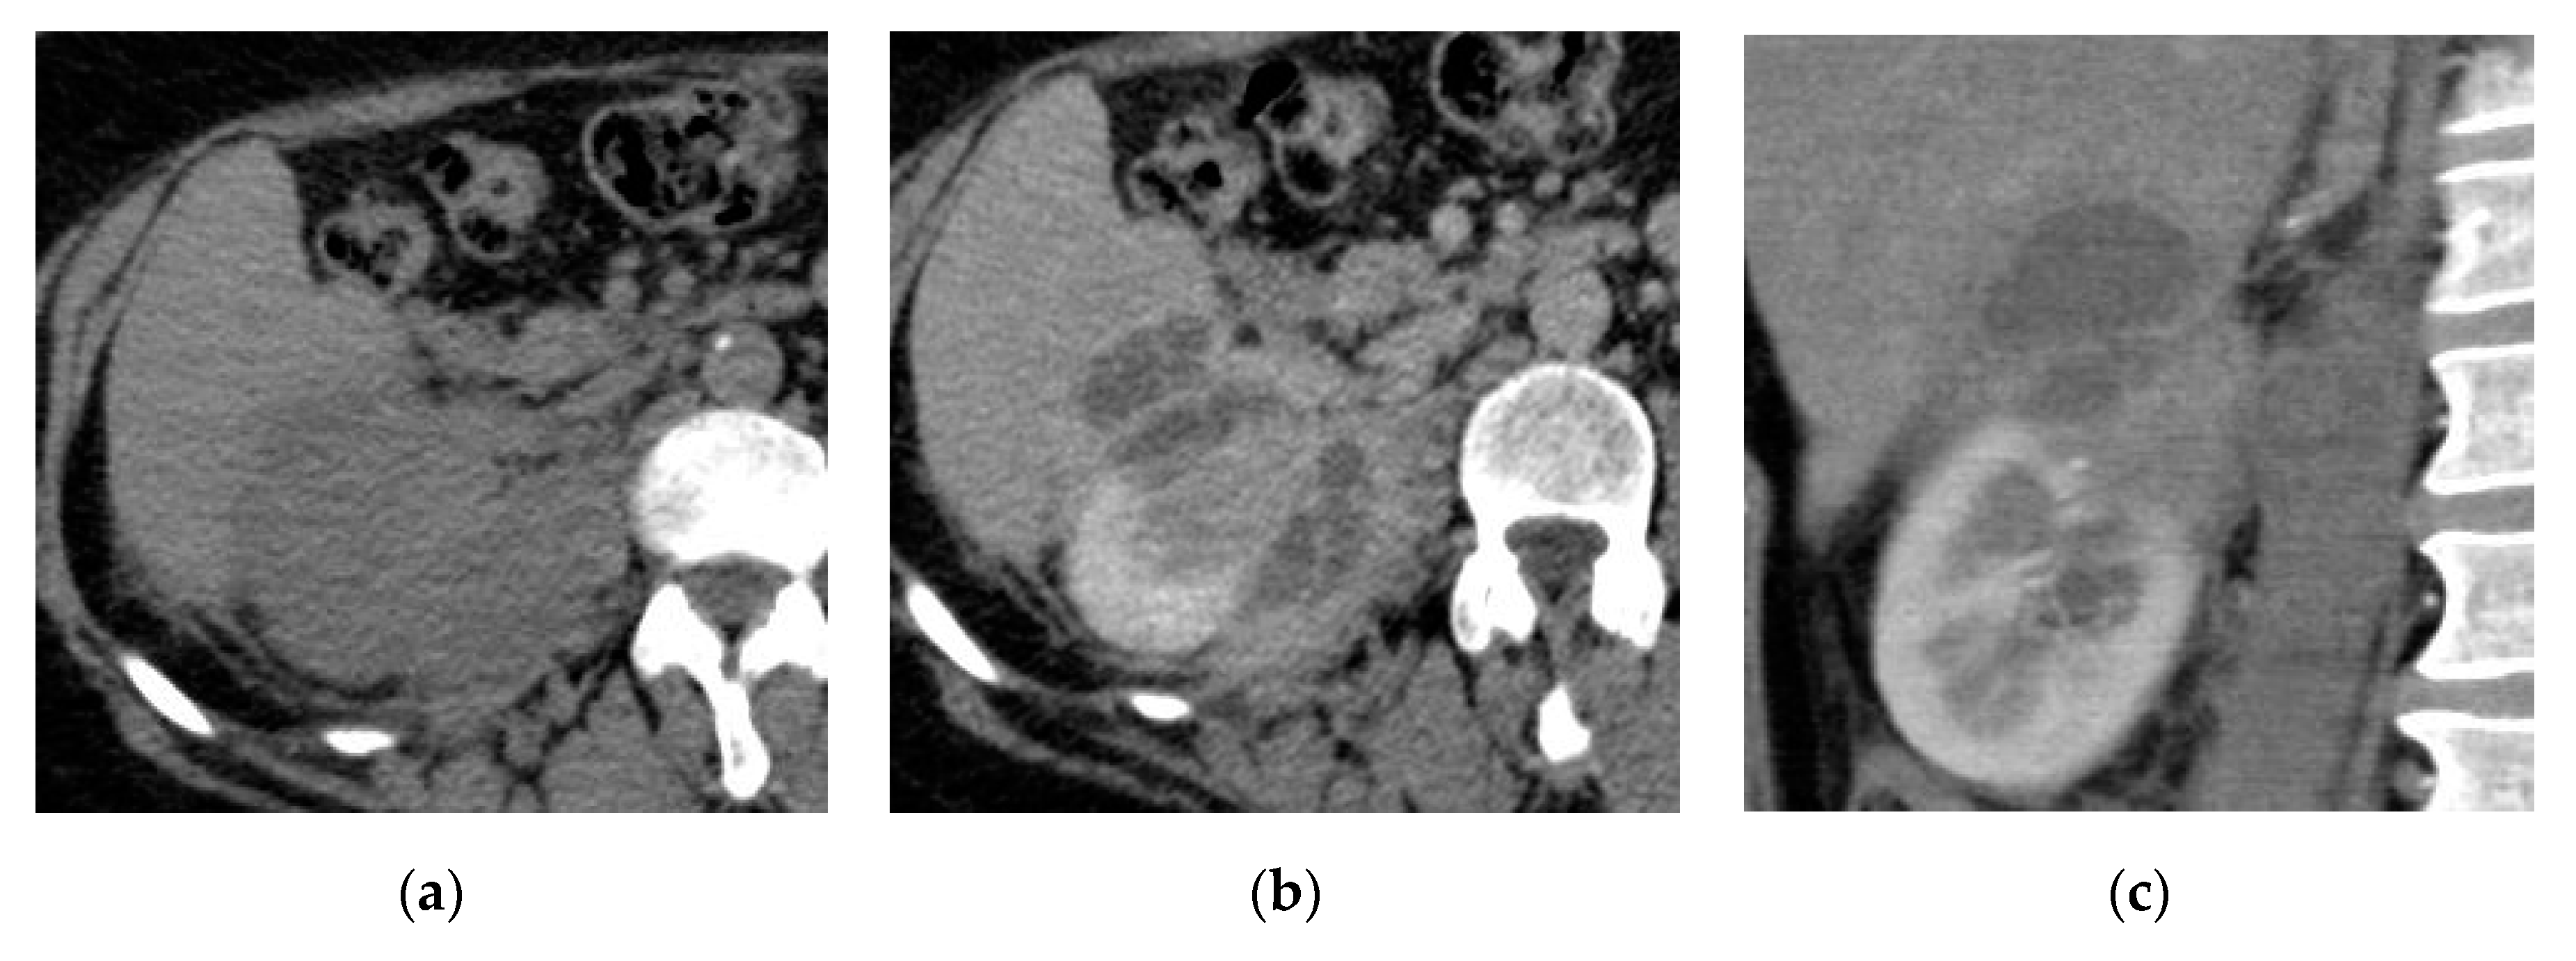

2.2. Renal and Perinephric Abscesses

| Renal abscesses | Round or geographic non-enhancing central fluid collection and enhancing rim. Perinephric fat stranding and thickening of Gerota’s fascia. |